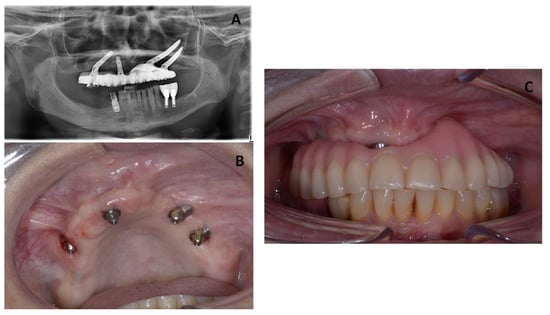

In the first follow-up appointment after one month, the patient exhibited healthy oral tissues with no signs of complications. A final Toronto prosthesis was delivered at six months after implant insertion (Figure 5).

The patient was recalled for clinical follow-up every 3 months for the first year, and then twice a year. In these appointments, any changes or complications and any adverse events were evaluated, and the occlusion was examined carefully. Additionally, the Toronto prosthesis was unscrewed to check the status of the soft and hard tissues. Figure 6 presents clinical and radiographic images taken at 3 years of follow-up, showing healthy peri-implant tissues.

Figure 5. (A) Radiographic images from the patient showing healing of the MRONJ lesions with two zygomatic implants inserted after one month of follow-up. (B) Clinical images from the patient showing healing of the MRONJ lesions with two zygomatic implants inserted. (C) Intra-oral view showing the final prosthesis.